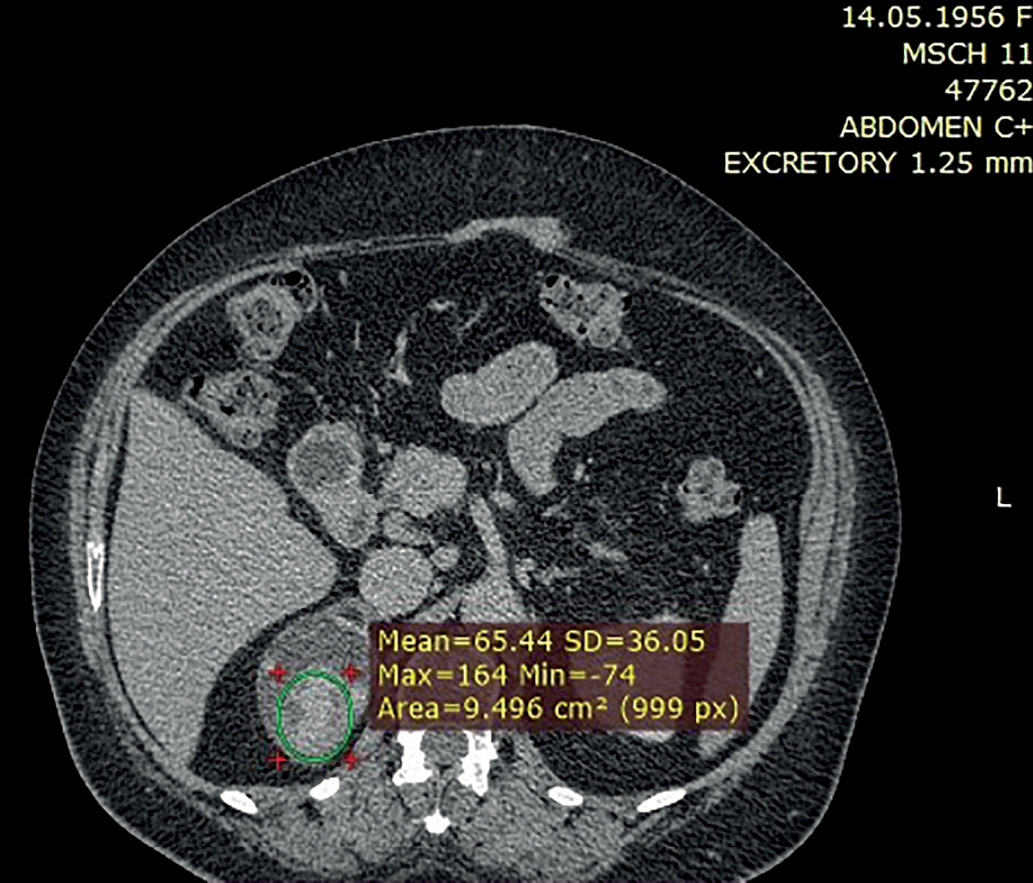

2. Рис. 2. КТ, отсроченная фаза. Участок с медленным вымыванием контраста. | |